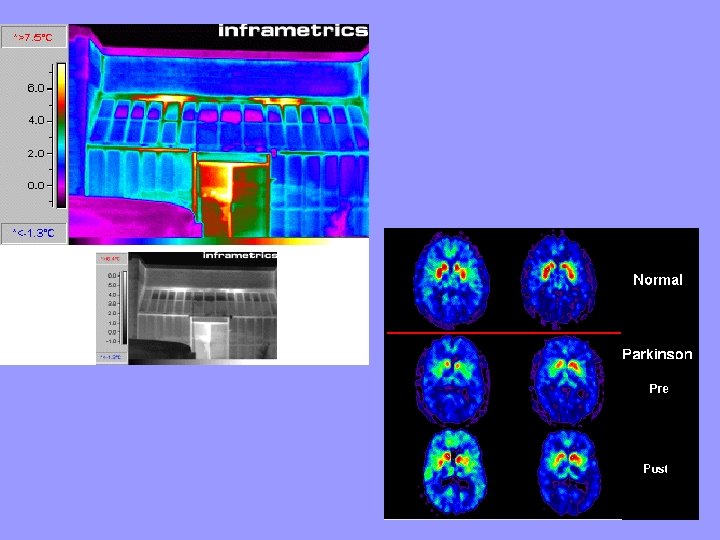

INFRARED RAYS • Infrared= “below red” • Shorter wavelength and higher frequency than microwaves. • Given off by objects as heat energy Ex. Heat lamps. • Thermogram—a picture that shows regions of different temperatures in the body.

X- RAYS • Shorter wavelength and higher frequency than UVrays • Carry a great amount of energy • Can penetrate most matter. • Bones and teeth absorb x-rays. (The light part of an x-ray image indicates a place where the x-ray was absorbed) • Too much exposure can cause cancer – (lead vest at dentist protects organs from unnecessary exposure) • Used by engineers to check for tiny cracks in structures. – The rays pass through the cracks and the cracks appear dark on film.